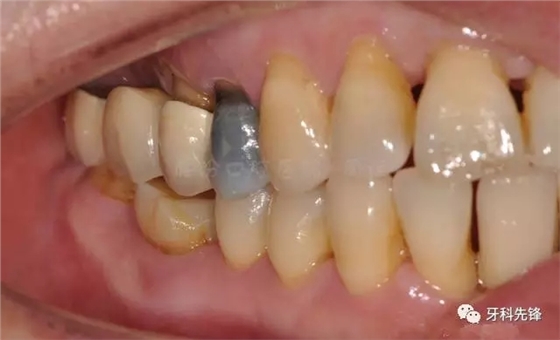

圖2 術(shù)前側(cè)位咬頜照

640.webp (3).jpg

圖5拆除原修復(fù)體側(cè)位咬合照

640.webp (6).jpg